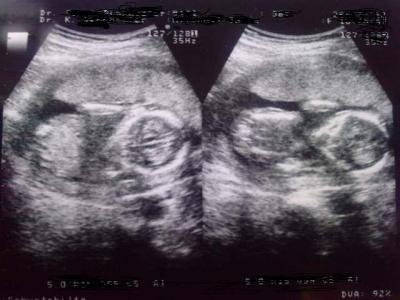

Hallo zusammen, hatte heute morgen um 8:30 Uhr mal wieder Termin beim FA. Mein Doc war sehr zufrieden mit uns. Urin war unauffällig, Eisenwert ist gut und Blutdruck sehr gut. Insgesamt habe ich bis jetzt 2,2 kg zugenommen. Vaginale Untersuchung war auch ohne Befund und der Muttermund "schön lang" *g*. Ach ja, CTG war ohne Auffälligkeiten also ohne Wehen. Unser kleiner Fruchtzwerg hat sich prima entwickelt und war wieder ziemlich fit. Outing haben wir leider keines bekommen, da mein Doc meint, es wäre ihm noch zu früh um das Geschlecht 100% bestimmen zu können. Wir haben schon anhand vom US-Bild gerätselt aber ich erkenn` da eh immer schwer etwas. Vielleicht habt ihr einen Tipp??? Richtig gelegen wäre es auf jeden Fall... Da ich aber schon so eine Vorahnung hatte, hab ich mir am Wochenende einen Test zur Geschlechtsbestimmung ersteigert (3..2..1..meins). Mal ducken was der anzeigt... Anbei noch 2 Bildchen (rechts der Kopf und zwischen Kopf und Rumpf die Ärmchen, Beinchen weiss ich gar nicht wo die sich verstecken *g*). Nächster FA-Termin in 4 Wochen. Da ich keinerlei Beschwerden habe, möchte ich nicht alle 2-3 Wochen hin. Kostet nur viel Zeit und (der Krankenkasse) Geld und zu oft möchte ich grundlos auch keinen US. Ach ja, also die exakten Ergebnisse hab ich von der Blutuntersuchung vor 4 Wochen (bei der NFM) noch nicht aber wir liegen bei ca. 1:2500. Statistisch gesehen lieg ich in meinem Alter bei 1:218 "Yippieh Yaeh". Liebe Grüße und weiterhin alles Gute!!!

Bild zu Heutiger FA Termin - Forum für August - Mamis